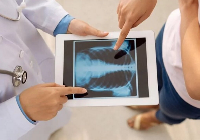

Выезд травматолога-ортопеда, рентгенолога Александра Валерьевича Дидковского.

На рабочем месте производится обучение работе на Вашем оборудовании.

Любого доктора можно быстро подготовить как рентгенлаборанта и дать необходимые знания для оценки рентгенограмм.

Изучение проблемы низкого качества рентгенограмм на Вашем оборудовании.